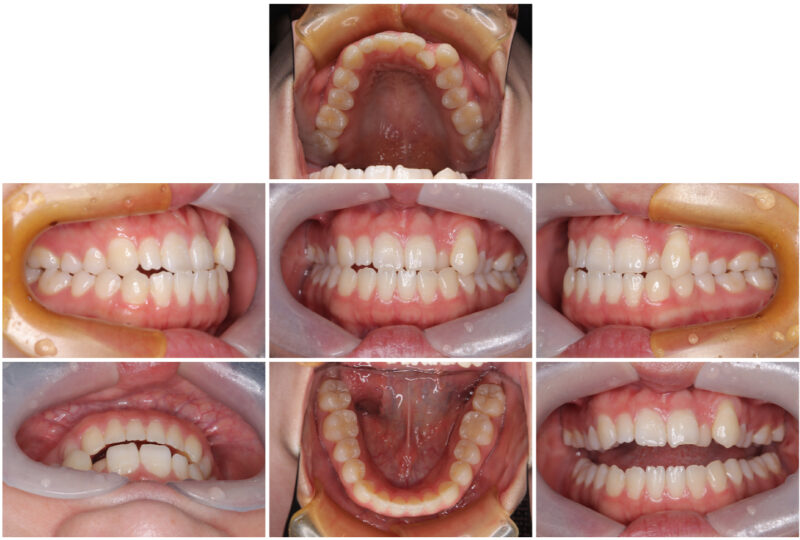

では実際にどんな写真を撮っているのか!

こんな感じで撮っています📷

ちなみに一眼レフなので画質はとても良いです✨

正面や側方、あとは食事で物を噛む面(咬合面)の部分などさまざまな視点から撮っています!